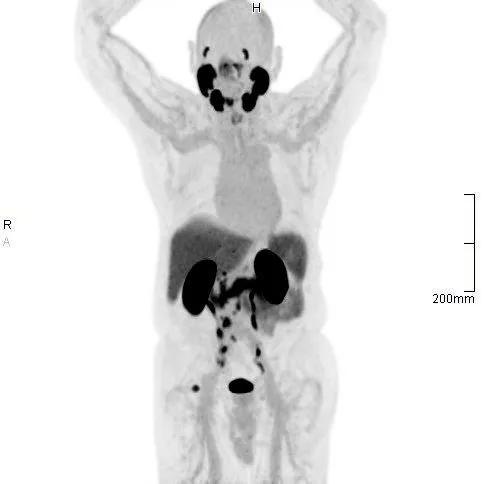

PSMA is a protein present at a low level in normal prostate tissue but occurs at much higher levels on the surface of prostate cancer cells. Tagging the PSMA protein with a radioactive tracer makes it is easily detectable on PET scans. “When combined with a CT scan or MRI, PSMA PET is substantially more likely to detect recurrent or metastatic prostate cancer than standard imaging techniques,” says Jacobo Kirsch, MD, Chair of the Cleveland Clinic Florida Imaging Institute.

According to Dr. Kirsch, the addition of PSMA PET/CT to Cleveland Clinic Florida’s imaging arsenal has already identified a number of cases of metastatic prostate cancer that would have been missed by other radiotracers or imaging modalities alone. “Finding these metastases earlier, when they are much smaller, has a significant impact on treatment planning and hopefully will mean better outcomes for our patients,” he adds.

In one case, a 66-year-old patient more than six years out from a radical prostatectomy had a PSA of 0.236 ng/mL during routine follow up, which represents a minimally elevated level. After a CT scan found no evidence of metastatic disease, a subsequent PSMA PET/CT identified seven very small bone lesions within the spine, scapulae, and ribs.

This case demonstrates one of the two current indications for PSMA PET which are: 1) high-risk men who are candidates for initial definitive therapy, such as prostatectomy or radiation therapy; and 2) men treated for localized prostate cancer with suspected recurrence based on rising PSA levels.

“PSMA PET imaging is able to find smaller metastases than other imaging modalities while exposing patients to substantially lower radiation,” says Dr. Kirsch. “With our state-of-the art digital PET/CT at Cleveland Clinic Florida, we achieve a high degree of detectability and can characterize the smallest of lesions.”